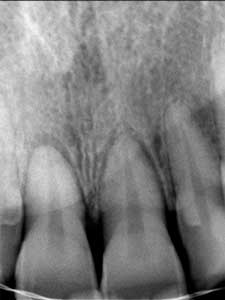

Se toma radiografía periapical con el radiovisiografo, encontrando zona radiolúcida periférica a los dos alvéolos, al retirar la férula los dientes se salen solos en condiciones desfavorables para su reinserción periodontal.

Radiografía Periapical

Dientes Centrales